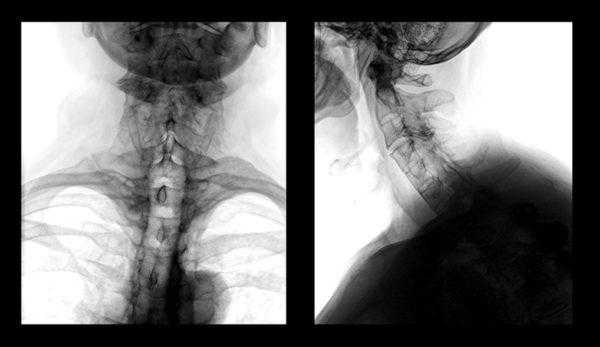

Укладка при рентгенограмме первого и второго шейного позвонка (атланта, осевого позвонка) в ПЗ проекции

Полную протяженность шейного отдела позвоночника можно увидеть только в положении сбоку. Если же снимок делается в прямой проекции, тень от нижней челюсти будет закрывать первый и второй позвонки. Чтобы получить качественное изображение, потребуется сделать прицельный снимок через открытый рот пациента.

При явных признаках смещения одного или нескольких позвонков шейного отдела, врач назначает рентгенографию позвоночника (спондилографию). При вероятном смещении Атланта (первого позвонка) рентгенография производится через рот.

- Рентгенографии ШОП. Рентген шейного отдела позвоночника с захватом затылочной кости в прямой и боковой проекциях позволяет визуализировать место сращения. На стандартных и функциональных рентгенограммах часто обнаруживаются признаки нестабильности СIV-СV и СV-СVI, которой сопровождается ассимиляция атланта: изменение высоты межпозвонковых дисков, смещение позвонков и нарушение параллельности их суставных поверхностей.